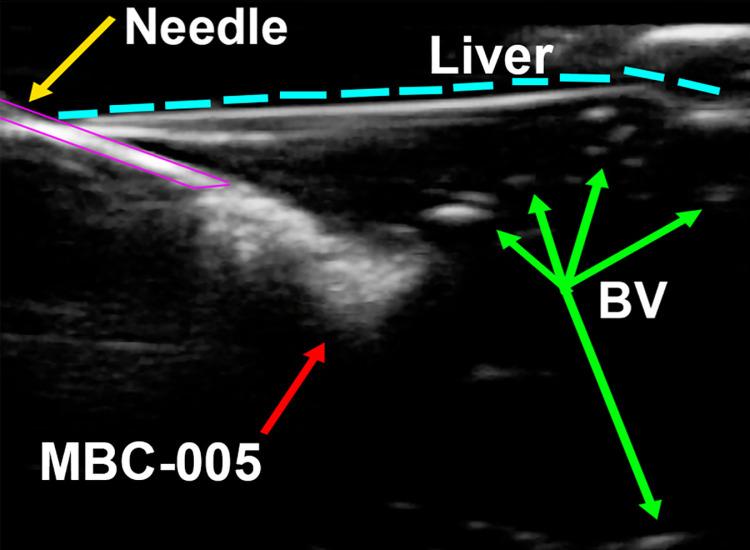

Patients with disseminated metastatic disease from breast cancer are likely to have liver involvement in >50% of cases at some point during disease progression. These patients have a poor prognosis; and, when treated with the standard of care systemic therapy they have a median survival of <9-months. Increasing survival in breast cancer patients will likely require the administration of better therapies that are specifically targeted to treat distant metastases. One approach to increasing treatment efficacy for breast cancer liver metastases is through the application locoregional therapies. Locoregional therapies are an appealing interventional approach for breast cancer patients with liver metastases since these tumor lesions are accessible via minimally invasive procedures that can be administered using either ultrasound or CT imaging. Current locoregional therapies to treat breast cancer liver metastases are non-specific and have not produced significant increases in survival. The goal of this study was to design and test a targeted locoregional therapeutic intervention for breast cancer liver metastases. The lead candidate, a fixed-dose small-molecule drug called MBC-005, was tested in vitro and then the efficacy was evaluated in a BALB/c mouse liver metastases model. A novel formulation of N-allyl noroxymorphone hydrochloride incorporated into an alginate-based gel overcomes many of the limitations associated with the administration of small-molecule drugs, which include solubility, off-target toxicity, and enzymatic degradation. In vitro results demonstrated that MBC-005 mediated its anti-tumorigenic effect through a p21-dependent mechanism via a novel molecular pathway, in which N-allyl noroxymorphone component of MBC-005 stimulated the opioid growth factor receptor to increase p21 expression. Intratumoral administration of MBC-005 increased survival 3.9-fold in mice and significantly decreased tumor volume 4-fold. While many cytotoxic therapies increase p21 expression as a response to DNA damage, MBC-005 increased p21 expression independent cytotoxic DNA damage. MBC-005 did not induce off-target toxicity; and, as such, would be amenable to multiple rounds of administration. Nevertheless, it is notable that the positive effects of MBC-005 treatment on increasing survival and decreasing tumor volume in mice was achieved using a single dose.